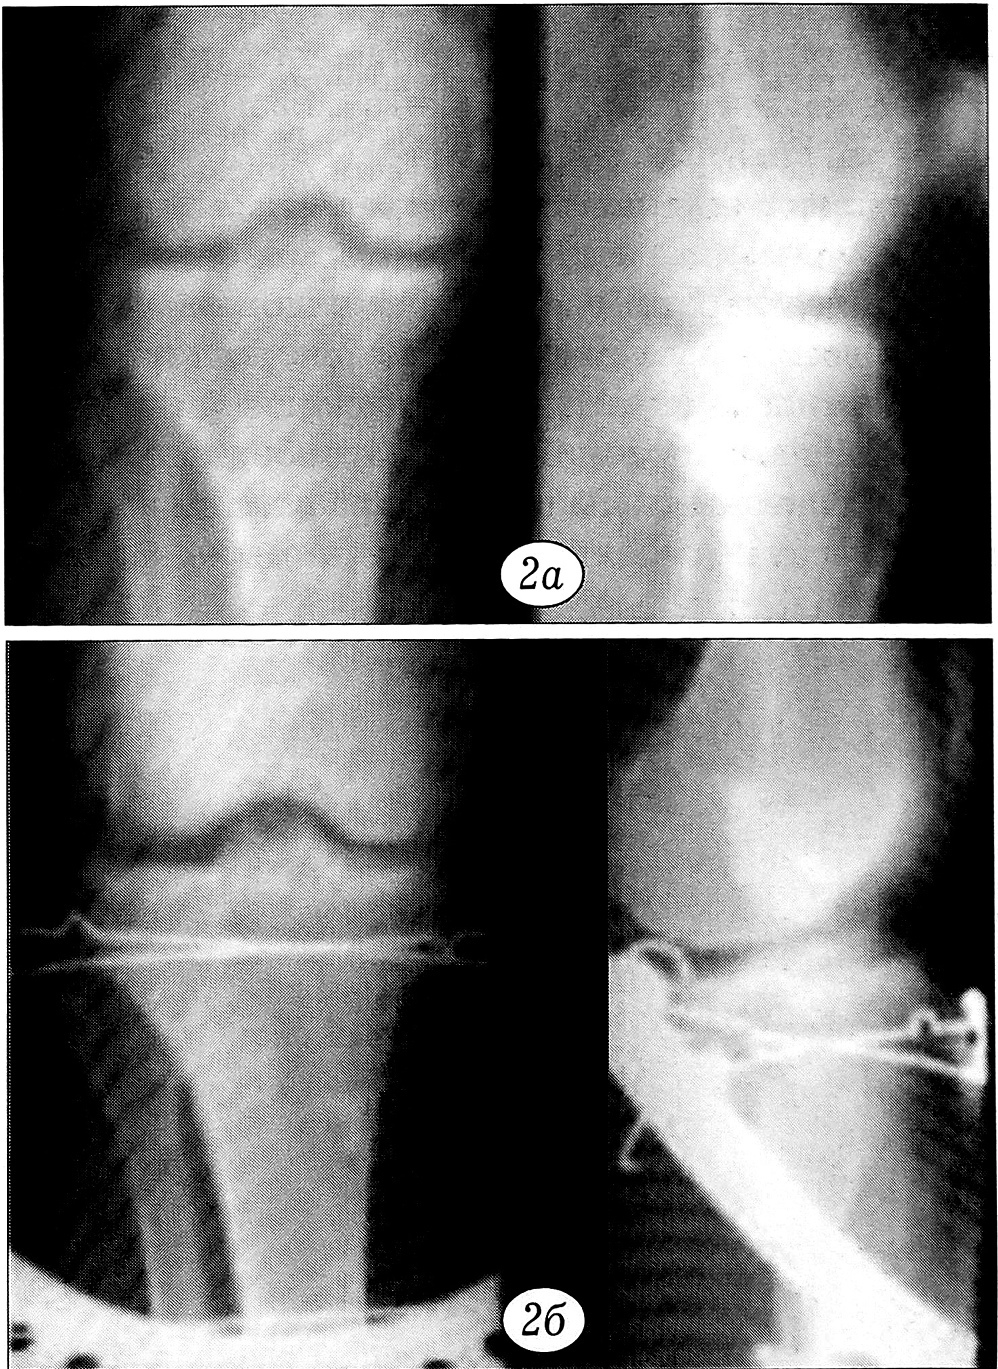

При переломах плато большеберцовой кости типа В1 («чистое» раскалывание одного мыщелка) аппарат Илизарова компоновали из одной дуговой опоры. Через мыщелки и верхнюю треть большеберцовой кости проводили 3~4 спицы, в том числе 2 с упорными площадками. Спицы проводили на двух уровнях, но фиксировали в одной дуге, расположенной под углом 30° к фронтальной плоскости. Репозицию осуществляли закрыто — путем ручного устранения смещения отломков по ширине и фиксации встречными спицами с упорными площадками. В результате одновременного натяжения спиц создавалась встречно-боковая компрессия отломков в плоскости излома (рис. 2). Опыт применения этой методики показал возможность использования для обезболивания местной анестезии. Подобные вмешательства мы производили зачастую в ургентном порядке, при поступлении пациента в клинику.

Рис. 2. Рентгенограммы больного 54 лет с переломом наружного мыщелка большеберцовой кости типа В1. a — до операции; б — после закрытой репозиции и фиксации в аппарате из одной дуговой опоры.